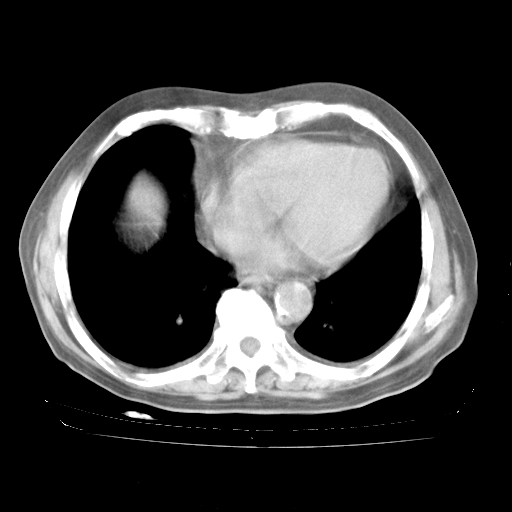

4月28日肺部CT——再次出现类似去年5月9日——透光度降低,“间质性”改变。

4月28日肺部CT——再次出现类似去年5月9日——磨玻璃样、间有“粟粒样”改变。